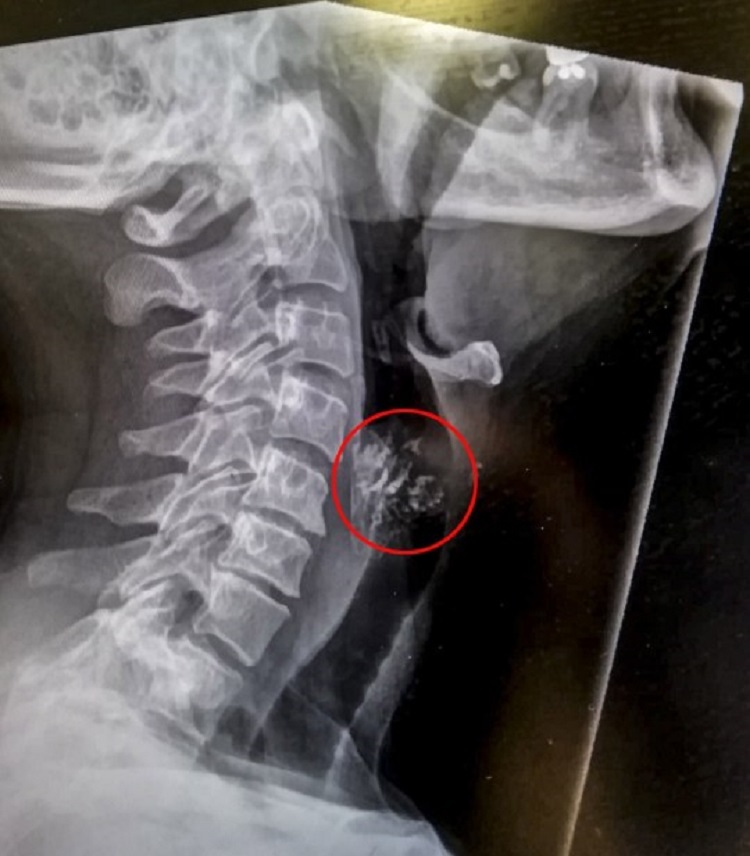

Angela, who works as a caterer, wasted no time going to the hospital where an x-ray revealed that her partial dentures were lodged half-way down her throat. The good news was that she didn’t choke but doctors said that pulling out the dentures out through her throat would do more harm than good and was advised to just let it pass.